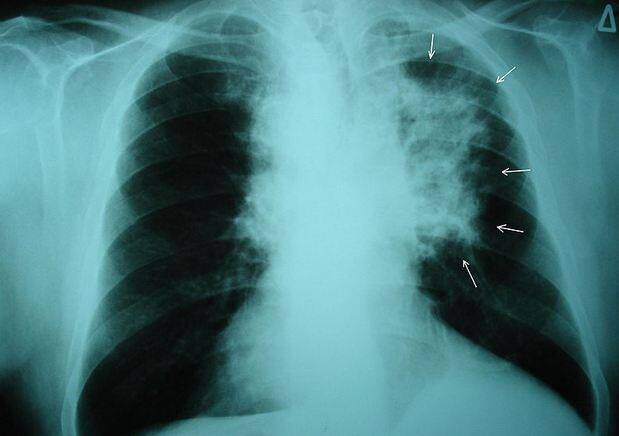

दिल्ली के प्रदूषण से अब लोगों को हो रहा है लंग कैंसर, डॉक्टर्स ने किया दावा

आमतौर पर ये माना जाता है कि लंग कैंसर की धूम्रपान मुख्य वजह है लेकिन ठोस सबूत हैं कि फेफड़े के कैंसर के बढ़ते मामलों में प्रदूषित हवा की भूमिका बढ़ रही है.फोटोः गूगल फ्री इमेज

अरविंद कुमार ने बताया कि फेफड़े का कैंसर खतरनाक बीमारी है और इसके निदान के बाद पांच साल तक जीवित रहने की उम्मीद होती है. धूम्रपान नहीं करने वाले युवाओं और महिलाओं में बढ़ते मामले को देखकर हम हैरान रह गए.फोटोः गूगल फ्री इमेज